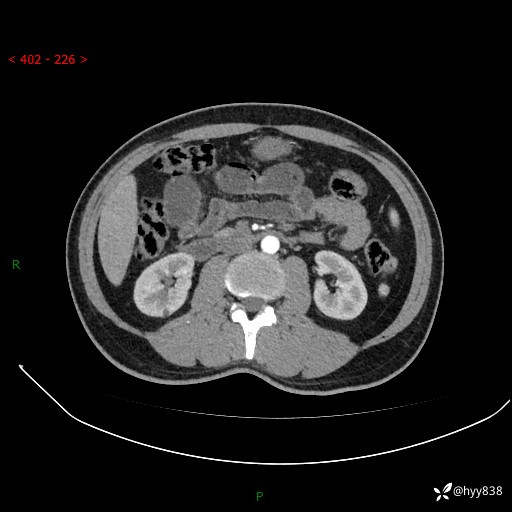

年轻男性,腹痛5月余。除了肠梗阻,你还能看到什么---结果公布~

主诉:腹痛5月余。

现病史:患者于5月前无明显诱因开始出现腹痛,上明显,为间断性胀痛不适,无畏寒发热,无心慌气促等特殊不适,遂来我院。我院门诊遂以“腹痛原因待查”收入我科。 起病以来,患者精神、饮食、睡眠欠佳,大小便正常。体力体重无明显变化。

腹部CT增强扫描(动脉期+静脉期)